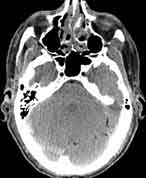

Visible Human male: Sectio transversalis 1124

CT

NMR

Pd T1 T2